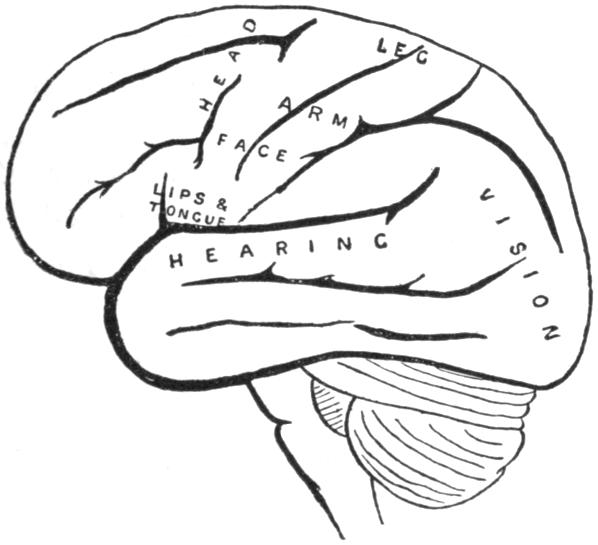

| VIII. | The Nervous System | H 117 |